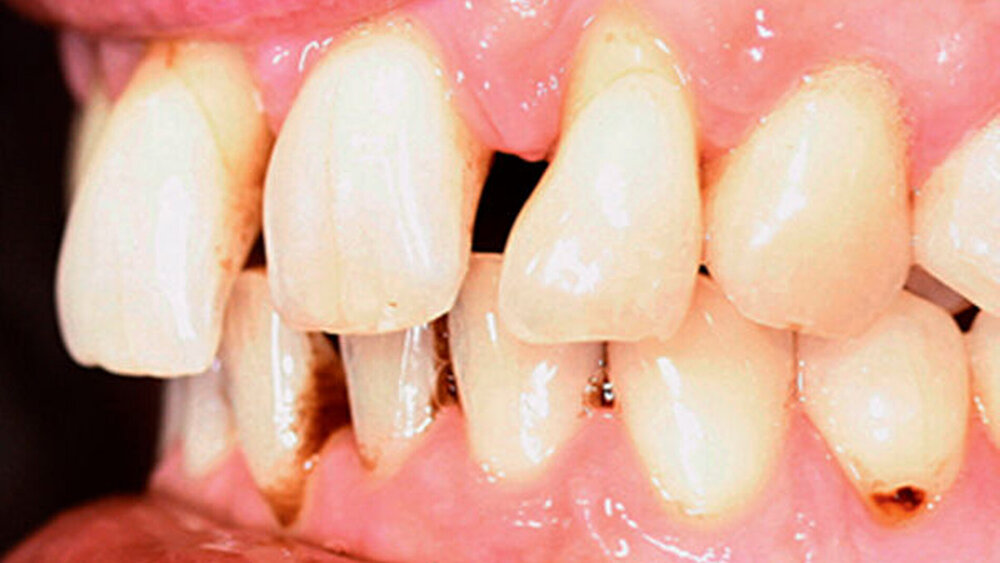

Anamnestisch lagen keine Besonderheiten vor. Es ist jedoch zu vermerken, dass ein regelmäßiger Alkohol-, Koffein- und Nikotinkonsum zugrunde lag. Intraoral zeigte sich ein bereits konservierend versorgtes permanentes Gebiss mit aktivem und inaktivem kariösen Geschehen. Große Anteile der Zahnhälse lagen nach Zahnfleischrückgang in Kombination mit Knocheneinbrüchen frei. Zahn 27 wurde bereits extrahiert.

Eine Beurteilung der parodontalen Situation an Zahn 11 offenbarte mesial und distal Sondierungstiefen von jeweils 6 mm.

Kieferorthopädisch imponierte beidseits eine neutrale Verzahnung bei einem tiefen Biss von 5 mm – bedingt durch die Verlängerung beider Frontzahngruppen. Besonders Zahn 11 zeigte eine erhebliche Verlängerung und Protrusion mit einer sagittalen Frontzahnstufe von 5 mm. Sowohl die Frontzähne im Ober- als auch im Unterkiefer wiesen eine lückige Beziehung zueinander auf (Abbildung 1).